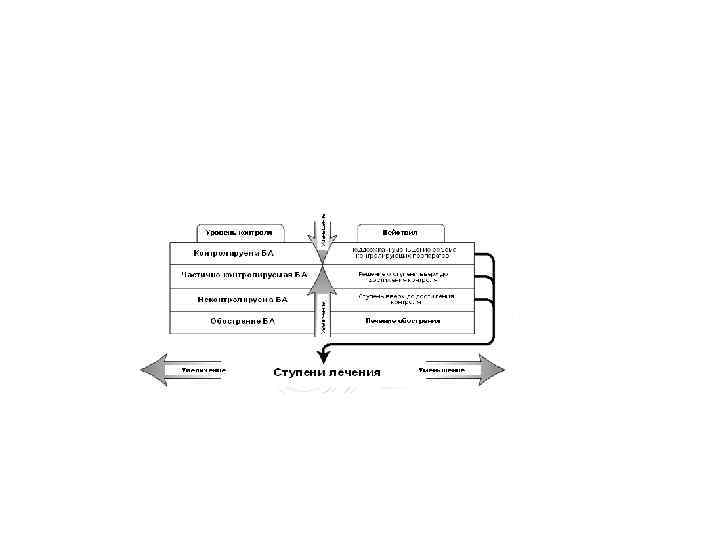

2. Степень тяжести течения (ступени): – – Ступень I – интермиттирующая астма (эпизодическая): симптомы - реже 1 раза в неделю; обострения заболевания короткие (от нескольких часов до нескольких дней); ночные симптомы менее 2 раз в месяц ; ОФВ 1 (ПСВ) >80% от нормы, суточные колебания < 20%. Ступень II - легкая персистирующая астма: симптомы проявляются от 1 раза в неделю до 1 раза в день; ночные симптомы возникают более 2 раз в месяц; обострения заболевания нарушают активность и сон; ОФВ 1 (ПСВ) >80% от нормы, суточные колебания 20 - 30%. Ступень III - персистирующая астма средней тяжести: ежедневные симптомы; обострения заболевания нарушают активность и сон; ночные симптомы возникают более 1 раз в неделю; необходим ежедневный прием бета – 2 агонистов короткого действия; ОФВ 1 (ПСВ) от 60 до 80% от нормы, суточные колебания более 30%. Ступень IY - тяжелая персистирующая астма: постоянные симптомы; частые обострения заболевания нарушают активность и сон; частые ночные симптомы; физическая активность ограничена, необходим ежедневный прием бета – 2 агонистов короткого действия; ОФВ 1 (ПСВ) < 60% от нормы, суточные колебания более 30%.

Степени тяжести

3. Фазы течения: – – – Фаза обострения. Фаза нестабильной ремиссии. Фаза стабильной ремиссии – не менее 2 лет полностью отсутствуют проявления заболевания 4. Осложнения: – – Астматический статус. Спонтанный пневмоторакс. Ателектаз легких. Беттолепсия – кратковременные обмороки во время пароксизма кашля в результате преходящей гипоксии мозга.